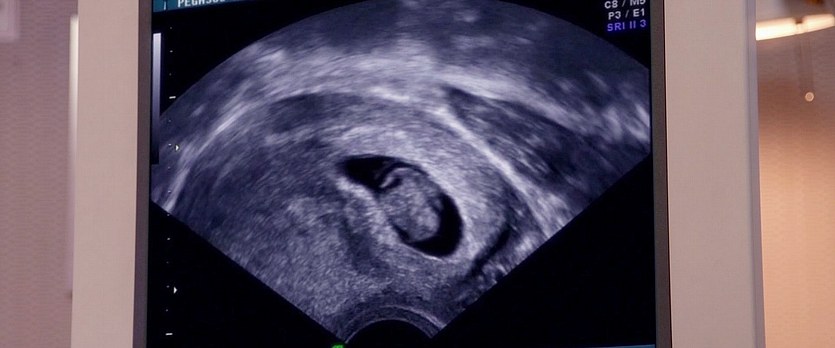

Hello Babies (2014)

Name: Hello.Babies.2014_05734

Source: Blu-ray 1080p